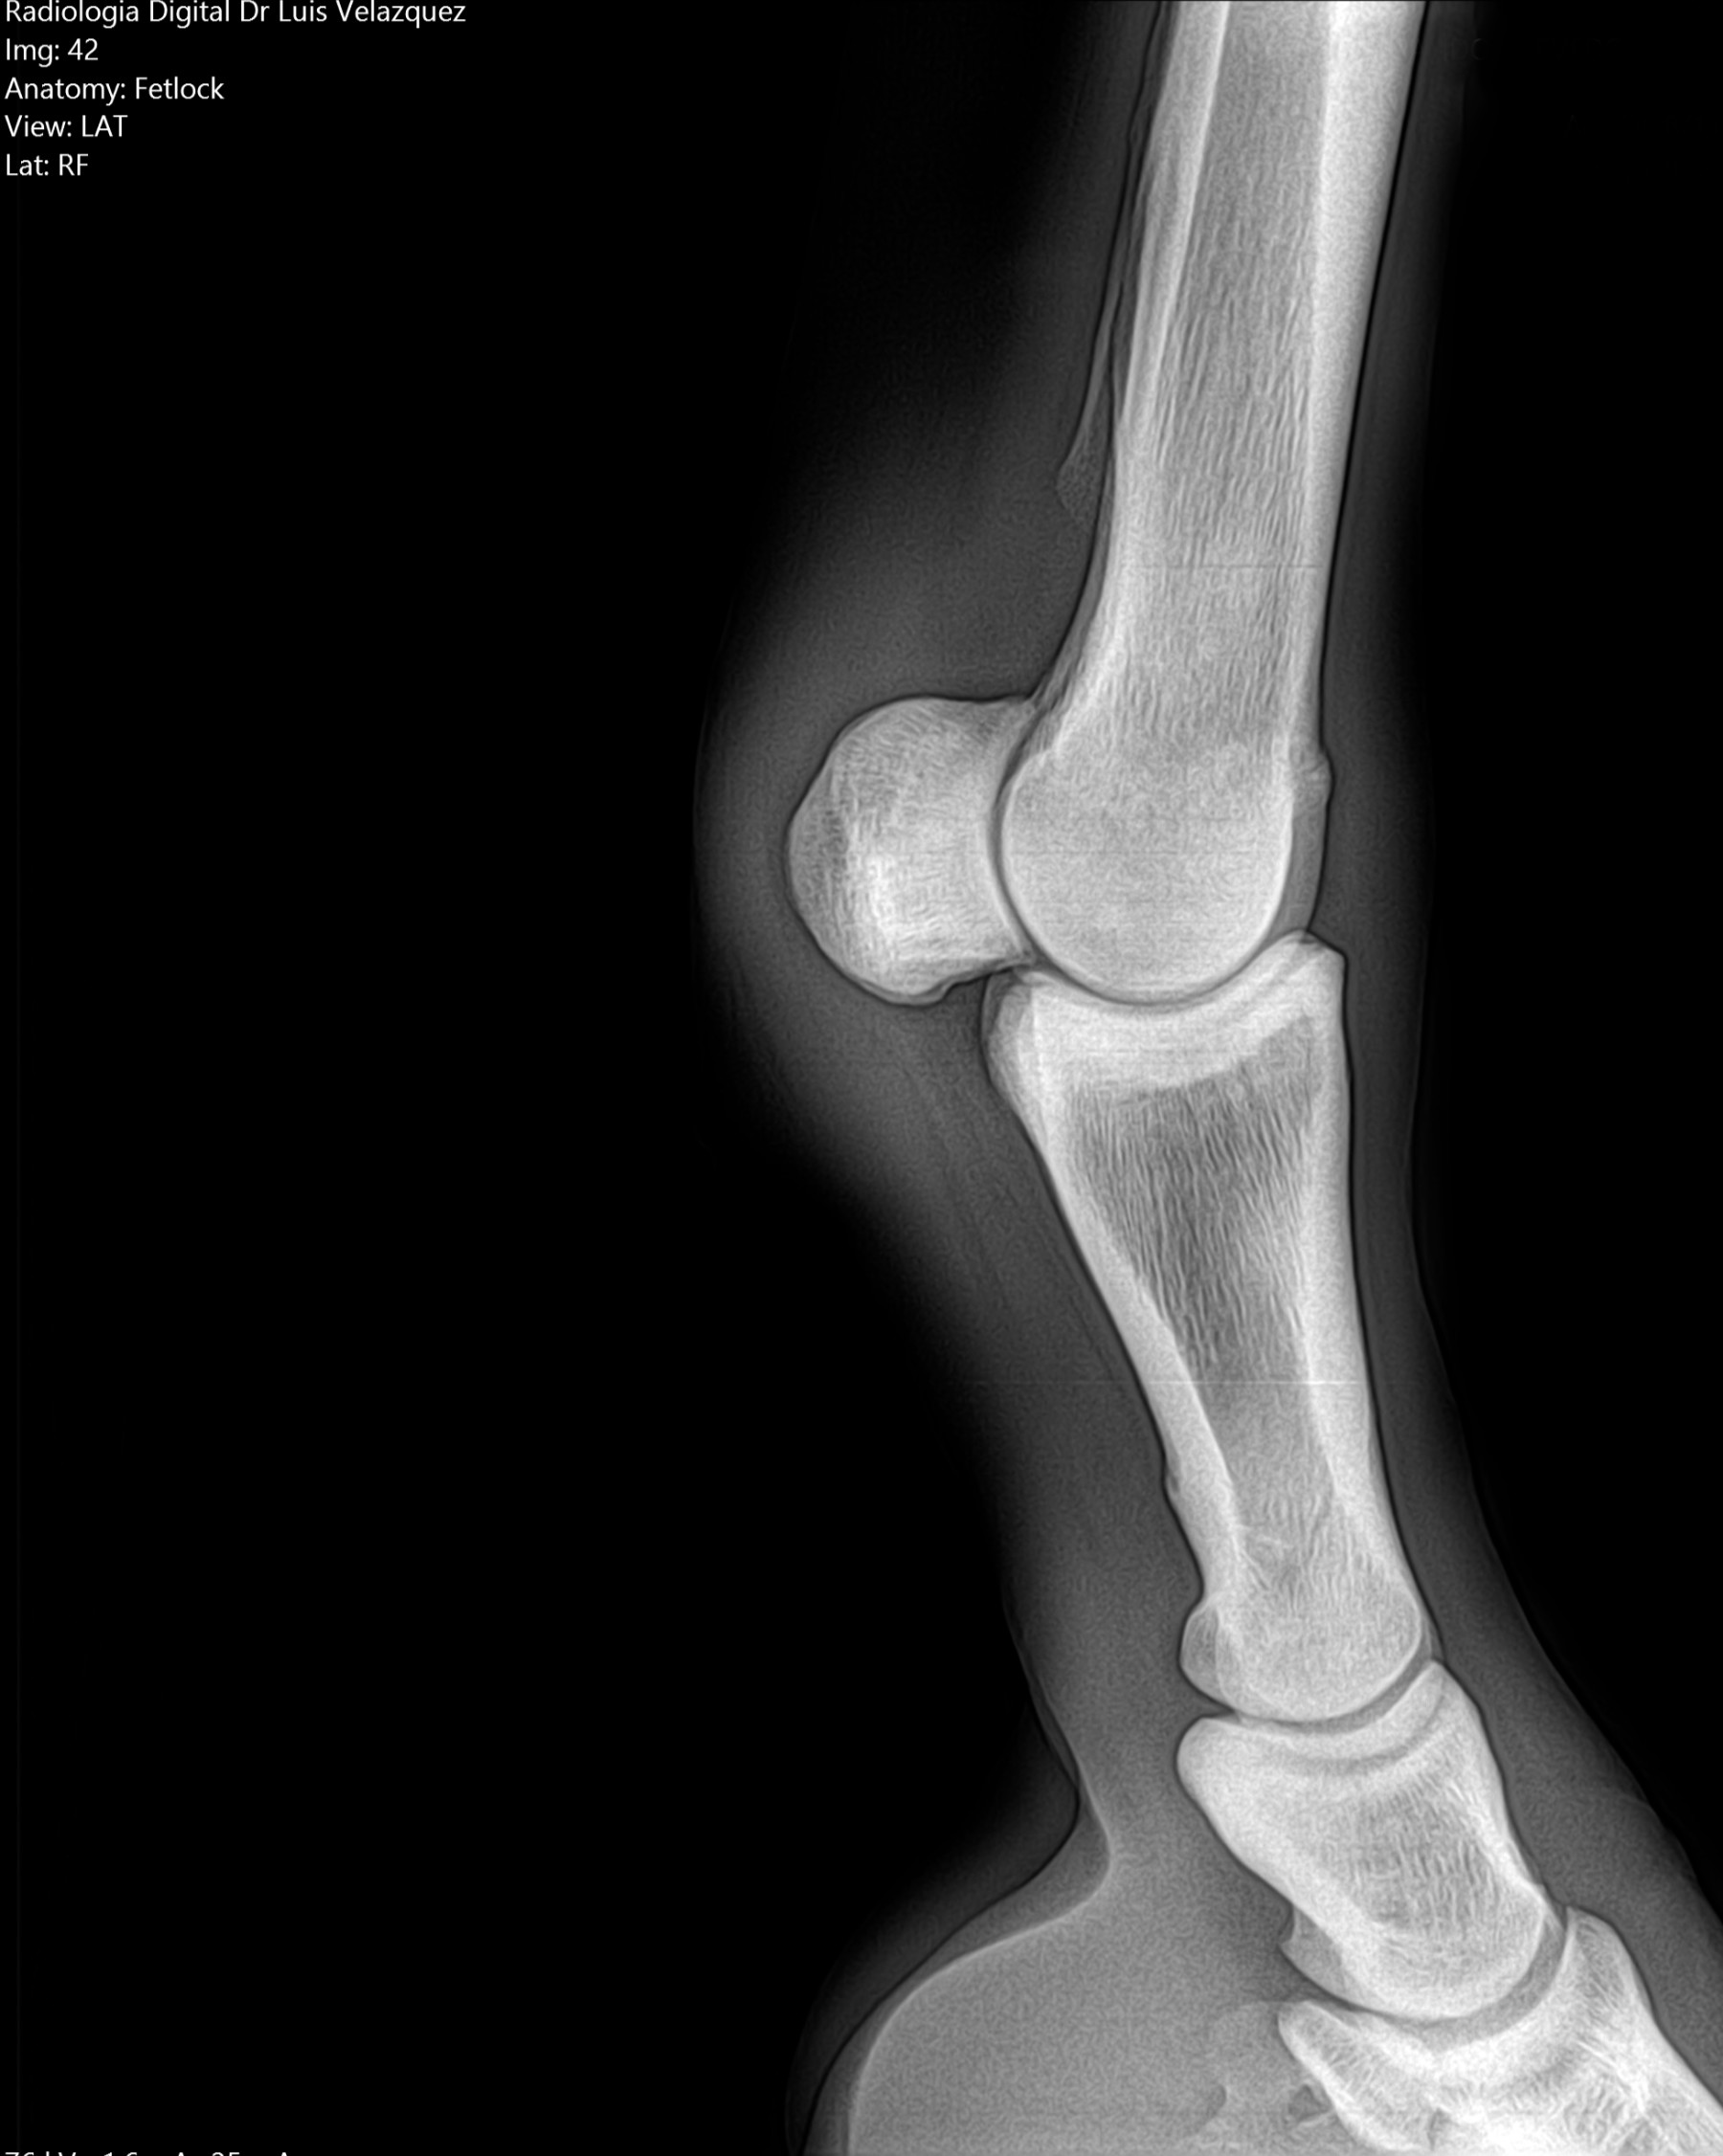

Cambios Térmicos en las Extremidades de Caballos,

Asociados a Golpes y su Evaluación por Termografía.

Los caballos de salto, en competencia, pueden derribar obstáculos y lastimarse. Si se golpean, no siempre claudican. Considerando al calor como un signo de inflamación, se evaluaron los cambios térmicos de 6 áreas de las extremidades torácicas y pelvianas de 23 caballos de salto en nivel de competencia de 1.05 a 1.60 m de altura, por medio de termografía durante 4 días de competencia (N=2208 áreas).